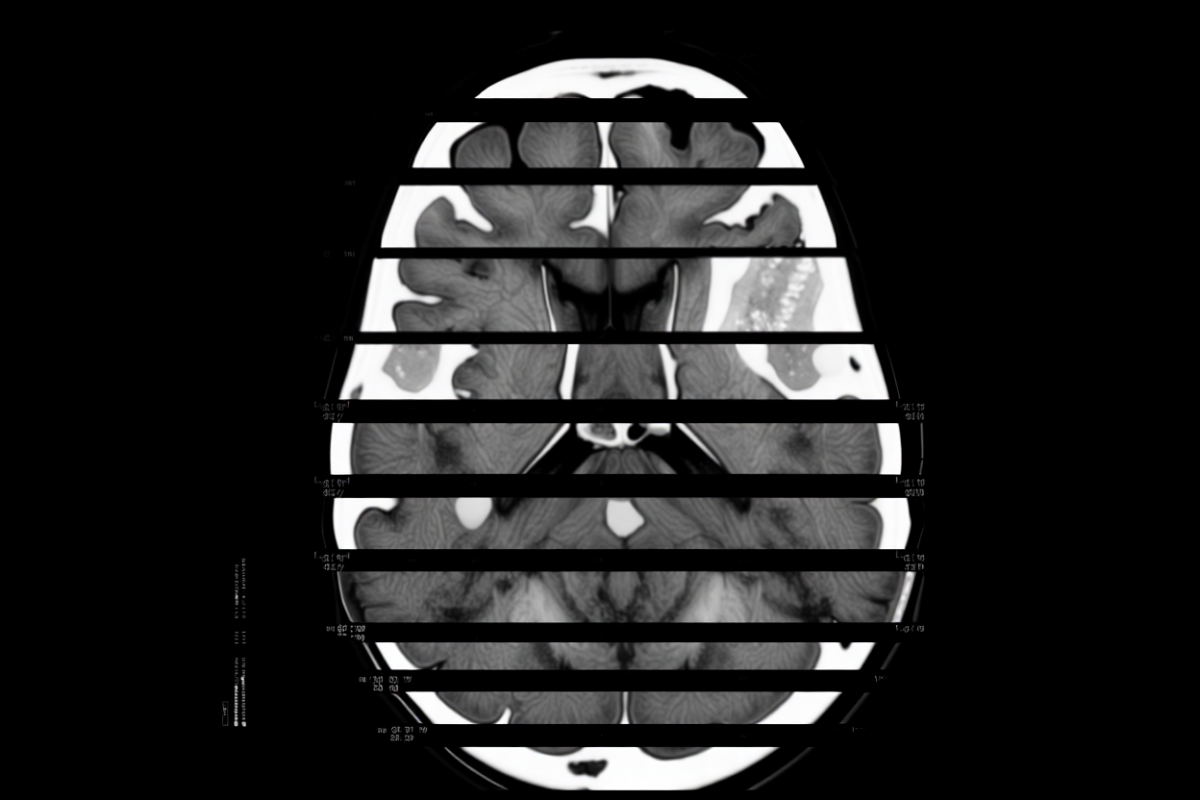

Здравоохранение в РоссииВ России разработан метод раннего выявления деменции с использованием искусственного интеллекта для анализа компьютерной томографии мозга. Об этом сообщил генеральный директор компании NtechLab Алексей Паламарчук.

С 2021 года компания внедряет медицинскую платформу, а в 2024 году получила регистрационное удостоверение Министерства здравоохранения РФ на собственное программное обеспечение, признанное медицинским изделием. Система искусственного интеллекта используется для анализа КТ-снимков мозга и уже внедрена в 12 регионах страны.

Текущая версия ИИ успешно определяет признаки инсульта и рассеянного склероза. По словам Паламарчука, на финальной стадии готовности находится модуль, позволяющий выявлять деменцию и болезнь Альцгеймера на раннем этапе.

Кроме того, компания разрабатывает технологию, которая позволит на основе анализа состояния мозга прогнозировать развитие неврологических заболеваний. Сейчас это решение находится в процессе государственной регистрации, пишет Газета.Ru.